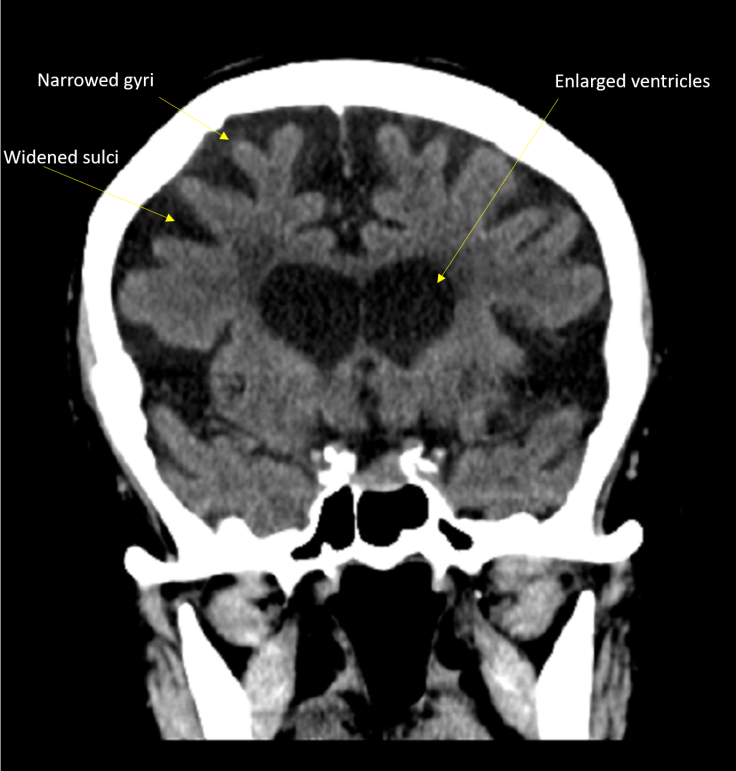

A normal adult loses about 0.2% of brain volume every year after middle age. Compared to young and middle-aged adults, the brains of the elderly have comparatively widened sulci, narrowed gyri, a thin cortical ribbon, and enlarged ventricles due to progressive brain volume loss, which, clinically, may contribute slower processing speed for cognitive tasks and other changes. Microglia-mediated synaptic pruning and other etiologies for decreasing cortical volume in the aged brain have been proposed and are under intense investigation. Regardless of etiology, persons in the oldest old category (85+ years), like the person depicted here, will always have some degree of atrophy, which may be accentuated if concomitant neurodegenerative and/or vascular disease is also present.